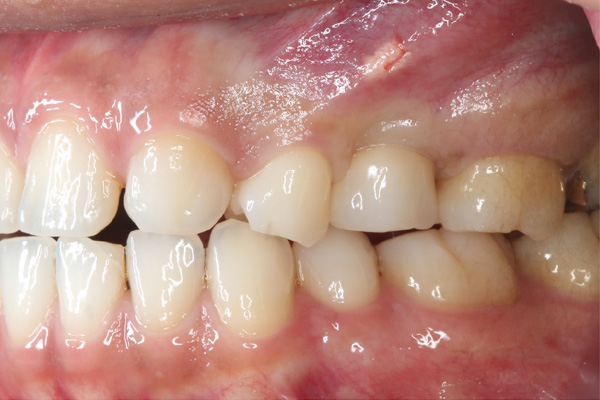

| 年代・性別 | 30代 男性 |

|---|---|

| 主訴 | 前歯が腫れた |

| 治療期間 | 約18ヶ月 |

| 費用 | 700,000円 |

| 治療内容 | インプラント、部分矯正、骨造成、結合組織移植、セラミック修復 |

| 治療に伴うリスク | インプラント周囲炎 セラミックの破折、脱離 |